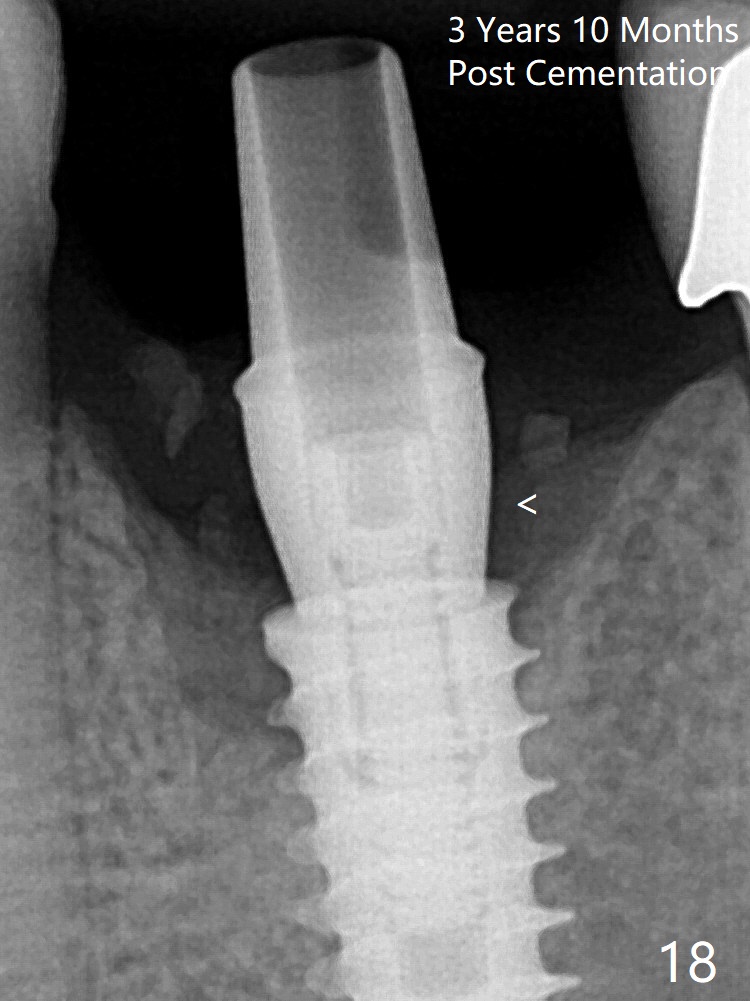

The crown/abutment is loose 3 times (3 months (Fig.14), 11 months (between Fig.14 and 15) and 2 years 3 months post cementation).  In spite of being stable 3 years 10 months post cementation, a smaller abutment is placed (Fig.17 (PA), 18 (BW)) with impression for a new crown.